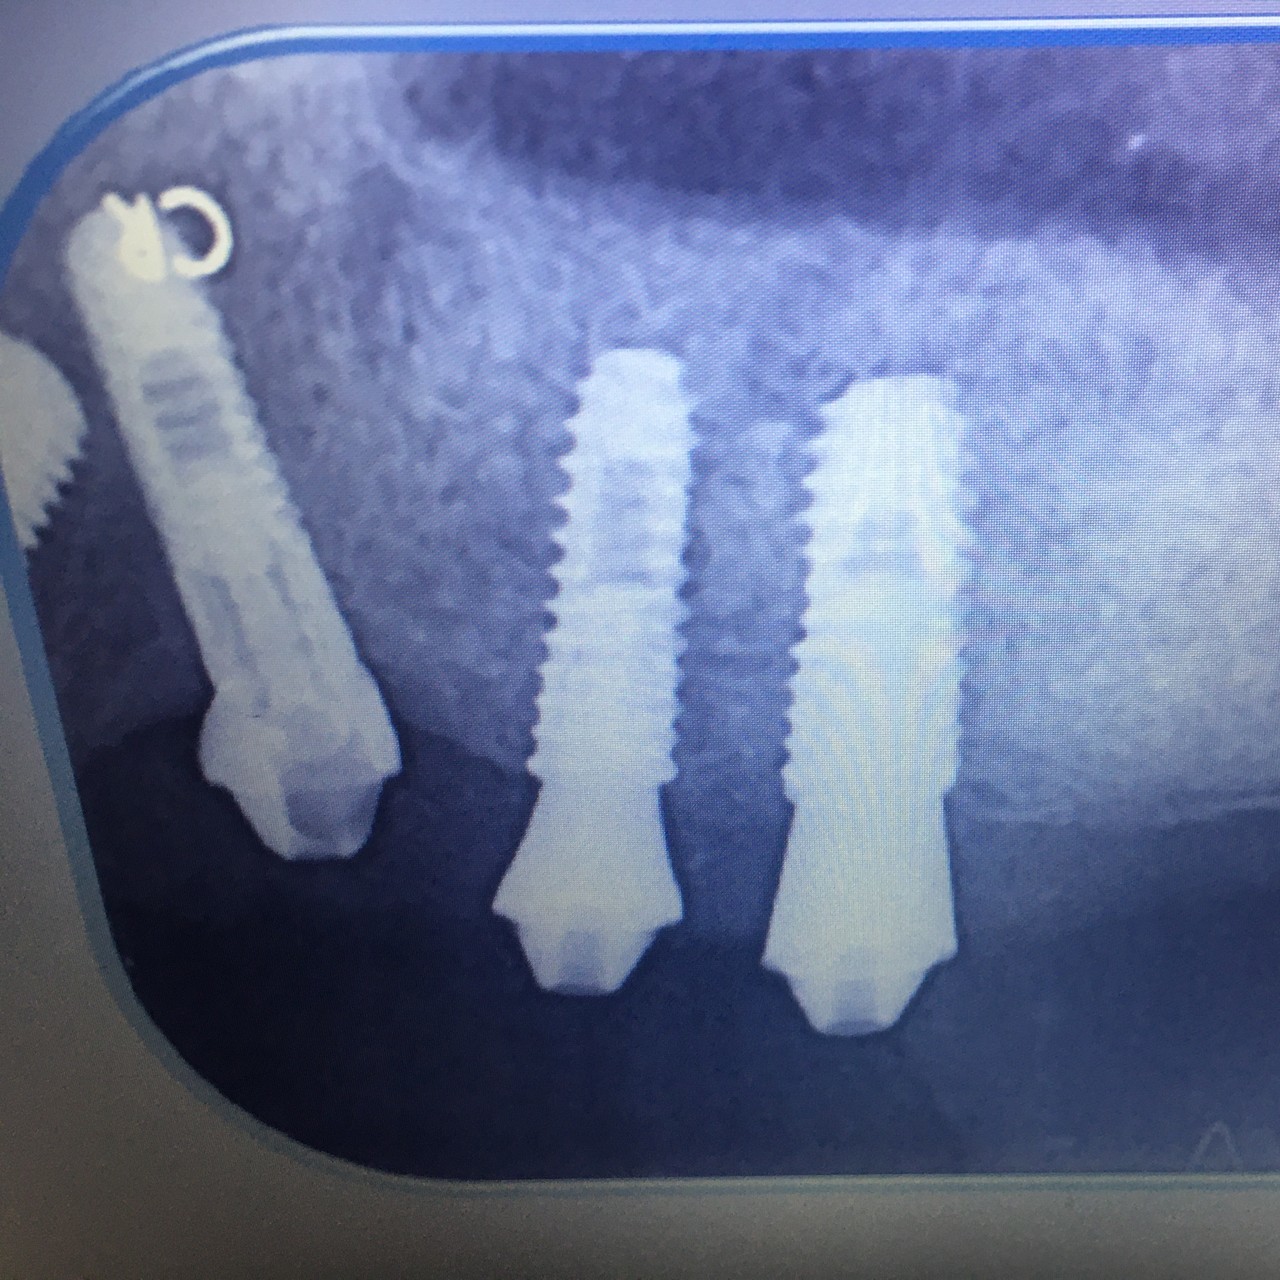

「オールオンX」とは、少ない本数のインプラントで、多数の人工の歯を固定する治療法の総称です。

「オールオン4」や「オールオン6」が代表的であり、オールオン4は、片あごにつきわずか4本のインプラントで12本前後の人工の歯を支えます。これは世界的に確立された治療法です。

オールオンXがまだ一般的に普及する前から20年以上(※)にわたり、当院では周りに先駆けてこの治療を行ってきました。治療の際、まず残っている歯を抜歯。その後4~8本のインプラントを埋め込みます。

私どもで行うオールオンX治療は、抜歯当日にインプラントを埋め込み、さらに仮歯を装着する「抜歯即時埋入」「即時荷重」に対応。これにより、従来なら複数回に分けて行っていた治療を短期間で進めることが可能になり、わずか半日で長年の歯がないお悩みから解放されます。症例によっては当日治療が難しい場合がありますので、ご了承ください。